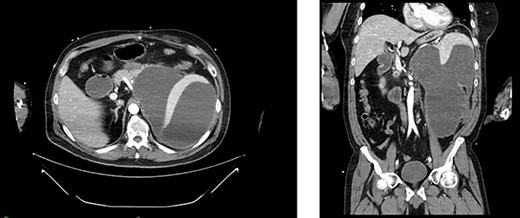

Two weeks post-resection, the patient was recovering as expected. At 4 weeks post-resection, radiation oncology recommended 7 weeks of intensity-modulated radiation therapy to both the surgical site and at-risk nodes identified on CT. Six weeks post-resection, the patient presented to the ED with nausea and vomiting. Abdominal CT revealed a retroperitoneal effusion at the surgical site (Fig. 3). At this admission, the patient also tested positive for COVID-19, delaying drain placement and his radiation treatments for 2 weeks.

Appearance of effusion in the left retroperitoneal space in transverse (left) and coronal (right) planes on CT; it can be seen encroaching on the spleen; subsequent cytology ruled of malignant effusion.